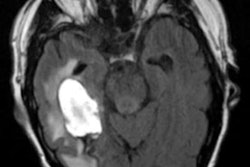

There are also some lingering concerns over performance and generalizability, as demonstrated by a recent study that detailed lower-than-expected sensitivity and positive predictive value from an intracranial hemorrhage detection algorithm after it was placed into clinical use. In addition, an international survey of more than 1,000 radiologists and radiology residents revealed divergent opinions on AI, with nearly 40% fearing being replaced by the technology.

Meanwhile, an AI algorithm shows promise for aiding the triage of potentially abnormal brain MRI exams. Also, a convolutional neural network designed to read dual-energy x-ray absorptiometry exams may help predict cardiovascular disease.